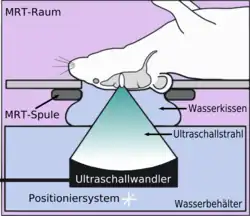

Die Blut-Hirn-Schranke lässt sich durch fokussierten Ultraschall öffnen. Dieser Effekt wurde erstmals 1956 nachgewiesen. Die Öffnung der Blut-Hirn-Schranke konnte durch die Anfärbung des Gehirns mit Trypanblau – einem Vitalfarbstoff, der normalerweise die Blut-Hirn-Schranke nicht passieren kann – und durch radioaktiv markiertes Phosphat nachgewiesen werden. Mikroskopisch konnten keine Veränderungen am Endothel beobachtet werden. Die Anwendung des Ultraschalls führte allerdings zu Hirnverletzungen.[137] 1960 wurde dann erstmals die Blut-Hirn-Schranke mit nur einer geringen Schädigung des umliegenden Parenchyms durch Ultraschall geöffnet.[138] Alle diese Versuche wurden mit hochintensivem fokussiertem Ultraschall, mit Leistungen im Bereich von 4000 Watt/cm², durchgeführt. Dabei entstehen Kavitationsblasen, die das Gewebe irreversibel zerstören können.[6]

- Fokussierender Ultraschall mit Mikrobläschen

Die Öffnung der Blut-Hirn-Schranke mit Ultraschall und gleichzeitig applizierten Mikrobläschen (Microbubbles) kam 2001 zum ersten Mal zur Anwendung.[139] Der Ansatz dabei ist, dass keine Kavitationsblasen generiert werden müssen, sondern injizierte Mikrobläschen die Funktion der sonst durch die hohe Ultraschallleistung erzeugten Kavitationsblasen übernehmen. Dadurch kann die Leistung des Ultraschalls deutlich reduziert werden; es besteht keine Gefahr mehr den behandelten Schädel, beziehungsweise das umliegende Gewebe, zu überhitzen. Die Technik ist mittlerweile so weit entwickelt, dass bei der Öffnung der Blut-Hirn-Schranke keine Apoptose, keine Ischämie oder sonstige Langzeitschädigung im Gehirn nachzuweisen sind. Wenige Stunden nach der Behandlung ist der alte Zustand der Blut-Hirn-Schranke wiederhergestellt.[6]

Der Fokus des Ultraschalls kann auf beliebige Areale im Gehirn gerichtet werden. Dadurch kann die Blut-Hirn-Schranke selektiv, auf bestimmte Hirnareale begrenzt, geöffnet werden. So können applizierte Wirkstoffe gezielt in diese Areale diffundieren.[140] Die behandelten Areale lassen sich durch eine simultan laufende Magnetresonanztomographie (MRT) genau verfolgen. Dabei dringt das für die MRT verwendete Kontrastmittel, beispielsweise Gadopentetat-Dimeglumin, nur durch die geöffneten Areale der Blut-Hirn-Schranke in das Gehirn ein. Diese Bereiche werden dadurch im MRT deutlich sichtbar hervorgehoben. Das hochpolare Gadopentetat-Dimeglumin ist nicht in der Lage die ungeöffneten Bereiche der Blut-Hirn-Schranke zu passieren.

Im Tiermodell Maus werden bei der Anwendung von fokussiertem Ultraschall mit Mikrobläschen Frequenzen im Bereich von 0,5 und 2 MHz[141] mit kurzen Pulslängen im Millisekundenbereich und Wiederholfrequenzen im Bereich von 1 Hz, über einen Zeitraum von weniger als einer Minute angewendet.[142] Der optimale Frequenzbereich liegt unterhalb von 1 MHz.[143] Die akustische Leistung beträgt weniger als ein Watt. Die verwendeten Mikrobläschen sind meist zugelassene Kontrastmittel aus der kontrastmittelverstärkten Sonographie. Sie haben typischerweise einen Durchmesser von 3 bis 4,5 µm, bestehen beispielsweise aus Humanalbumin und sind mit Perfluorpropan oder ähnlichen Schwergasen gefüllt.[144]

- Mechanismus

Der Mechanismus zur Öffnung der Blut-Hirn-Schranke durch die Anwendung von fokussiertem Ultraschall, zusammen mit Mikrobläschen, ist noch nicht vollständig aufgeklärt. Die Wechselwirkung von Ultraschall und Mikrobläschen spielt dabei eine große Rolle und führt in vivo zu einer Reihe von biologischen Effekten.[145] Eine wesentliche Rolle scheinen dabei Scherkräfte zu spielen, die durch Mikroströmungen erzeugt werden. Diese Mikroströmungen selbst kommen von Oszillationen der Mikrobläschen im Ultraschallfeld.[145] Von den Endothelien selbst ist wiederum bekannt, dass sie auf Scherkräfte dynamisch reagieren können und Scherkräfte eine kritische Größe für die Homöostase sind.[146] Elektronenmikroskopische Aufnahmen von Kapillargefäßen so behandelter Versuchstiere zeigen sowohl einen transzellulären als auch einen parazellulären Transport von entsprechenden Markermolekülen (Meerrettichperoxidase). Bei dem transzellulären Transport handelt es sich im Wesentlichen um Transzytose. Der parazelluläre Transport wird durch einen komplexen Desintegrationsprozess initiiert, bei dem die Tight Junctions ihre Funktion verlieren.[147]

Die so geöffnete Blut-Hirn-Schranke ist durchlässig für niedermolekulare Chemotherapeutika, wie beispielsweise Doxorubicin[148] und Antikörper, wie Trastuzumab.[149][150][151] Auch die prinzipielle Machbarkeit des Transports von Genen in das Gehirn wurde mit dieser Methode im Tiermodell nachgewiesen.[144][152] Das Verfahren zur Öffnung der Blut-Hirn-Schranke mit Ultraschall und gleichzeitig applizierten Mikrobläschen ist noch ein sehr junges Verfahren. Bisher wurde es nur an Versuchstieren erprobt. Bis zu einer möglichen Zulassung des Verfahrens am Menschen vergehen erfahrungsgemäß noch viele Jahre.